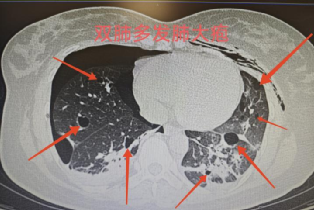

经胸部CT检查,李女士双侧肺叶弥漫分布多发肺大疱,部分大疱已破裂形成气胸。我院胸外科团队迅速组织多学科会诊(MDT),结合影像特征与患者病史,高度怀疑为罕见病——淋巴管平滑肌瘤病(LAM)。

CT表现

胸部高分辨率CT(HRCT):肺部弥漫分布的圆形薄壁囊腔(大小2—5mm至数厘米),囊壁均匀无分隔;